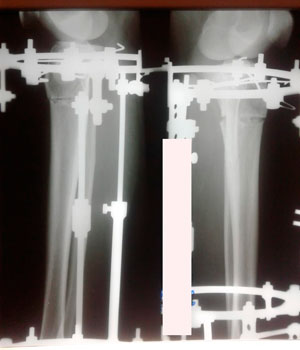

Исходник - 35 лет.

Дата операции - 07.11.2019г.

Диагноз: Варусная деформация голеней.

Вложения

IMG_6936-07-11-19-09-47.JPG

IMG_6933-07-11-19-09-47.JPG